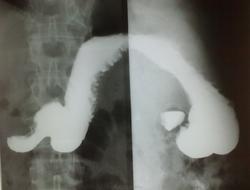

+1.Скорее всего, это не грыжа (пищеводного отверстия диафрагмы), а так получается пищеводая ампула( кратковременная картина "кольца сатурна "-инвагинация пищевода в пищевода - вариант нормы); т.к. дистальнее этого расширения видны тонкие пищеводные складки ( при грыже, были бы видны широкие желудочные складки слизистой).

ГПОД или нет - на откуп смотрящему. Рельеф слизистой гастритический: складки по большой кривизне разновеликие, неравномерные, избыточные, в антруме имеют косой ход (хотя полноценного раздувания двойного нет, судить адекватно не получится).

Ну, как Вы понимаете, по снимкам рельефа сторонний наблюдательно может напридумывать что угодно. Поэтому, если позволите, то по методике. Представлено 5 снимков. Каких нет? Нет прямого в вертикальном положении с контрастированной 12-перстной кишкой; нет лежа на животе с приподнятым левым боком и контрастированным пищеводом (именно в этой проекции определяется ГПОД), нет лежа на спине с приподнятым правым боком (для оценки пилоробульбарной зоны), нет левого бокового снимка стоя после снимков лежа (для оценки купола и задней стенки желудка). Снимок №4 (кроме того, что не контрастирована 12-перстная кишка) провоцирует больше вопросов, чем дает ответов: можно придумать дефект наполнения по малой кривизне в антральном отделе и пальцевое вдавление по большой по типу "перста указующего" (стрелки) И еще - гиперпластический гастрит, все-таки, достаточно редок, хронический гастрит, в основном, атрофический; неровность контура по большой кривизне в антральном отделе - является признаком хр гастрита (выход складок на контур); двуслойное содержимое луковицы 12-перстной кишки (газ и барий) - р-признаки бульбостаза (бывет еще 3-хслойное содержимое - барий-жидкость-газ) - косвенного признака патологии желчевыводящих путей.

единственное что увидел, так это ГПОД

Виктор, доьрый день.ГПОД я тоже увидела.